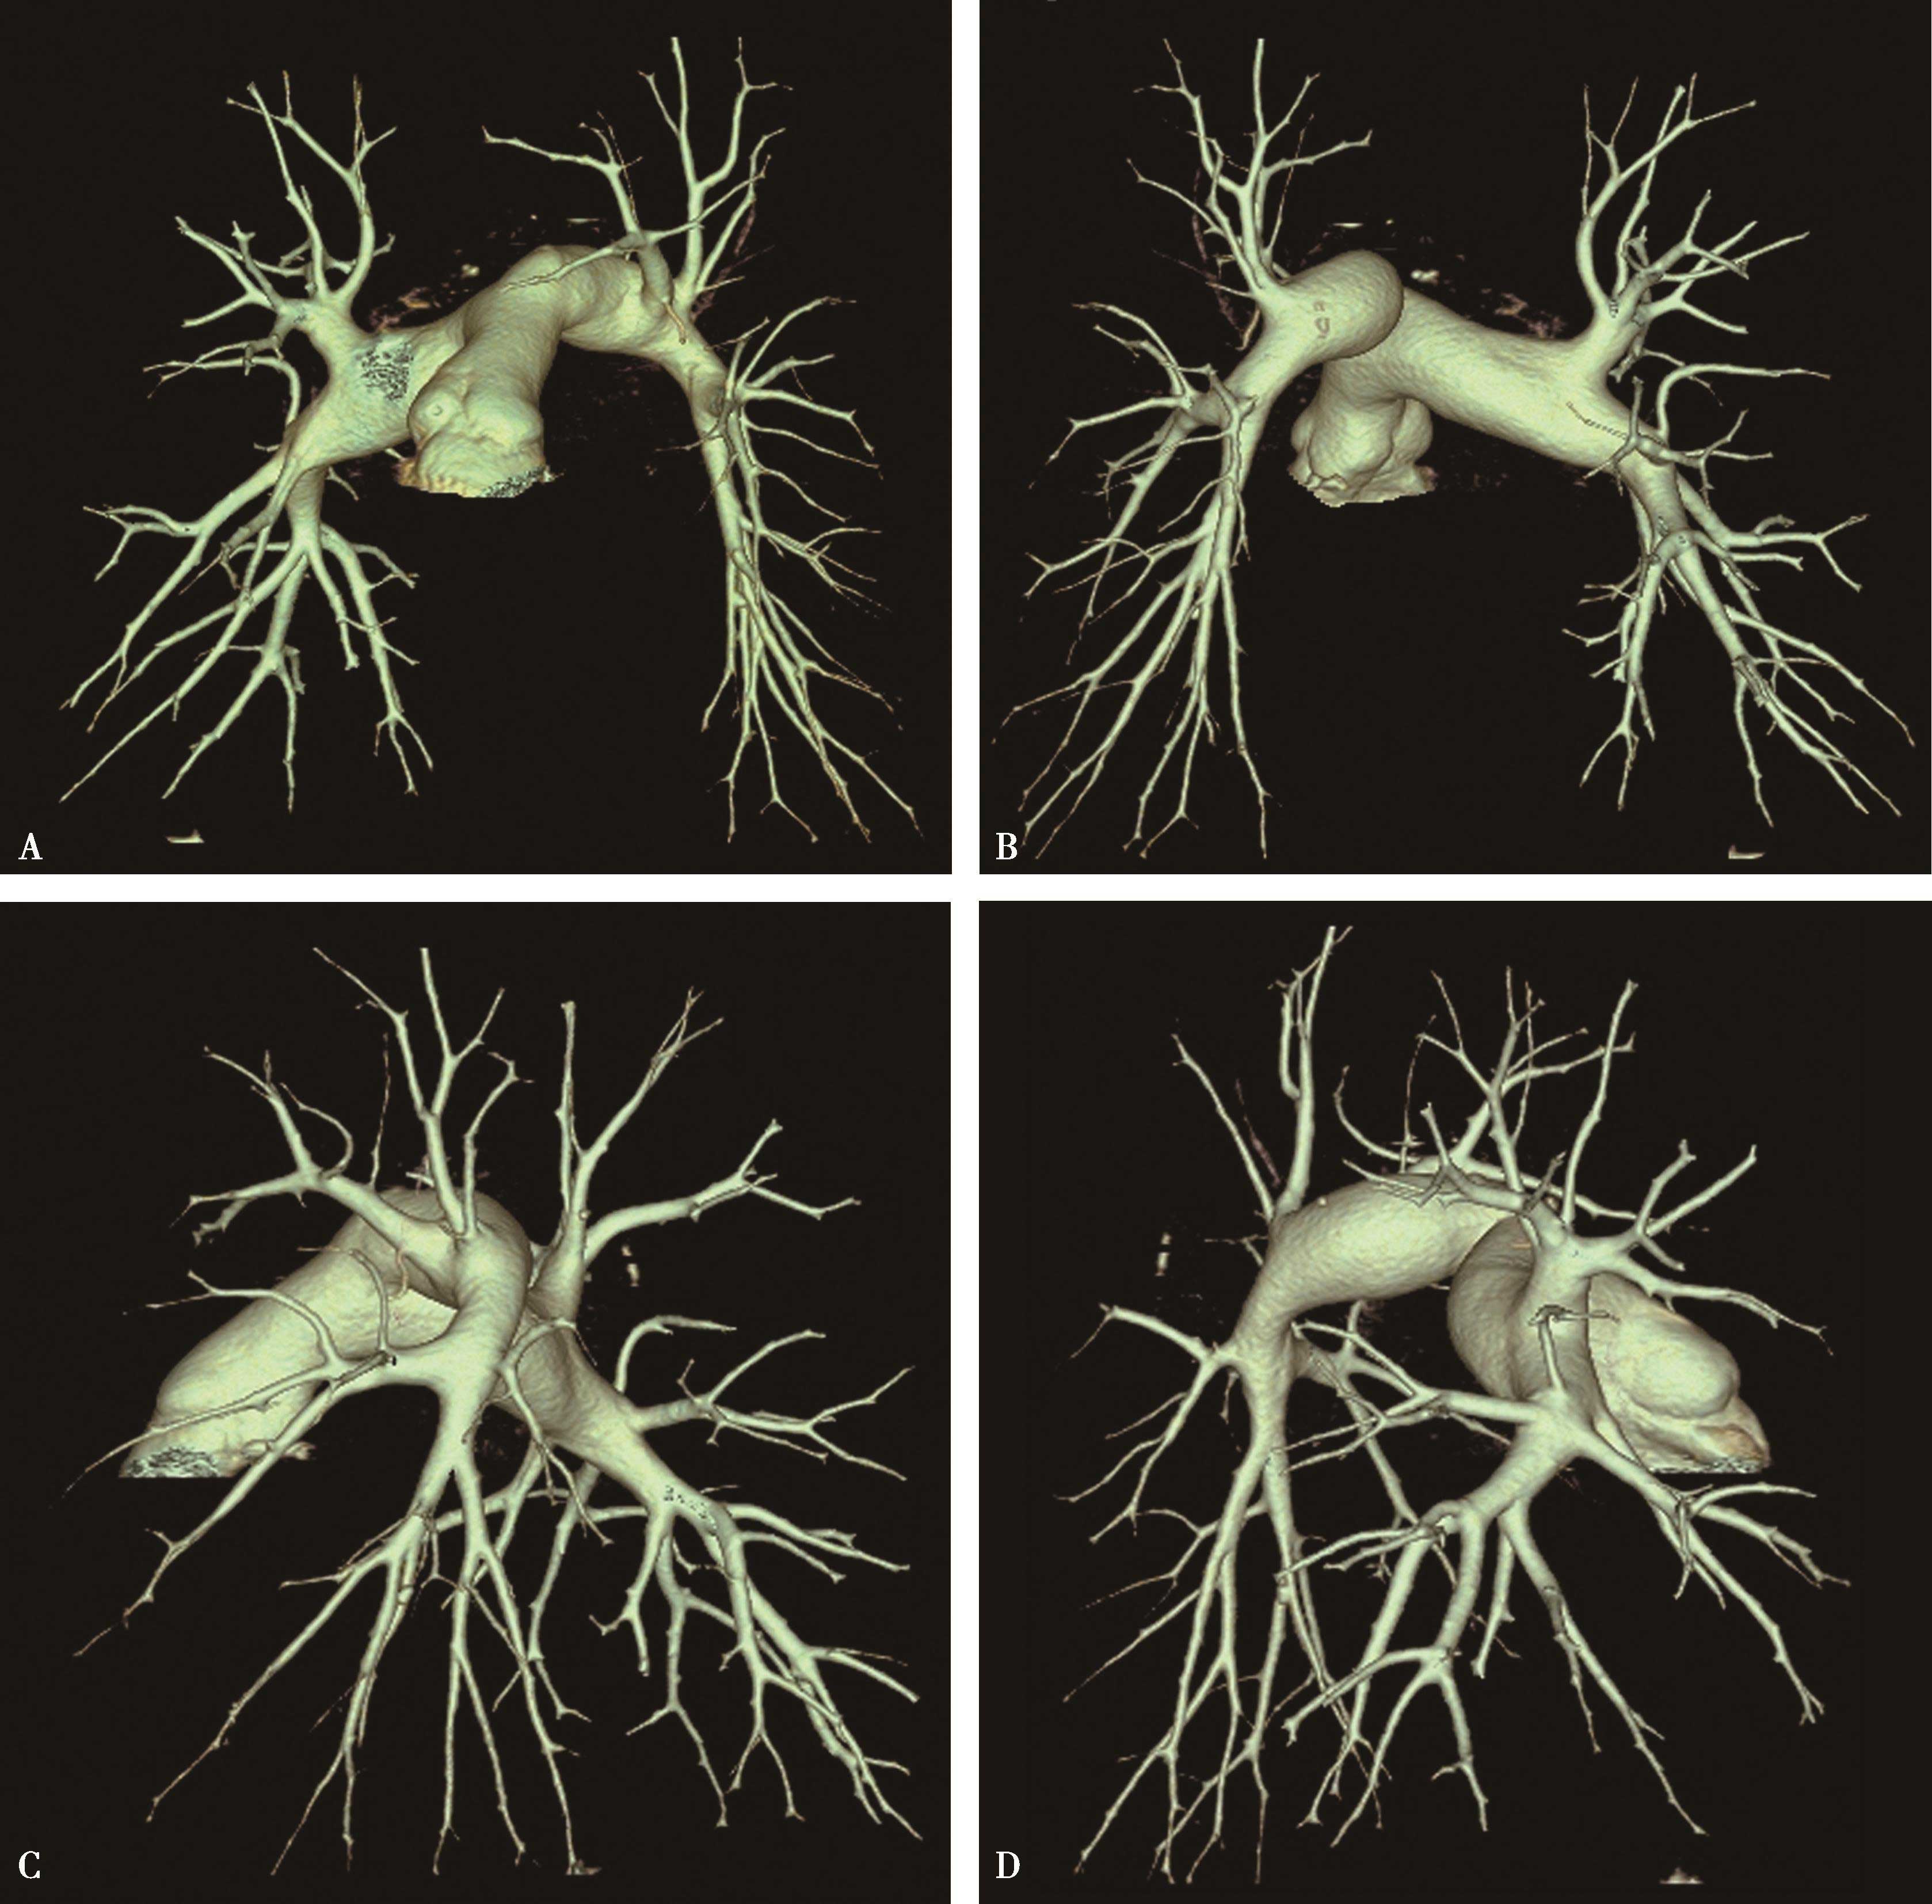

图8-2-1 肺动脉容积再现(VR)

正常肺动脉:A.冠状位;B.背面观;C.左前斜位;D.右前斜位